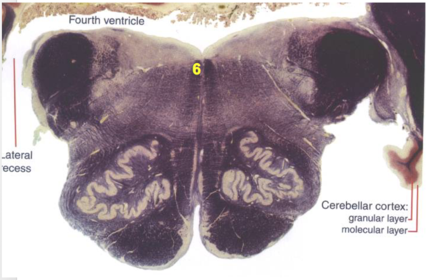

| CN IX | |

| Inferior cerebellar peduncle | |

| Inferior olivary complex | |

| Dorsal cochlear nucleus | |

| Inferior vestibular nucleus | |

| Medial vestibular nucleus | |

| Spinal nucleus of V | |

| Spinal tract of V | |

| Medullary pyramids | |

| Solitary nucleus | |

| ALS | |

| Medial lemniscus | |

| Medial longitudinal fasciculus | |

| Ventral cochlear nucleus | |

| Anterior spinocerebellar tract | |

| Central tegmental tract | |

| Olivary internal arcuate fibers | |

| Solitary tract | |

| Abducens root fibers | |